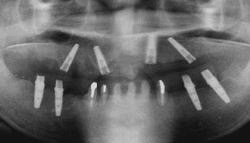

| 上顎、下顎共にグラツキの著しい歯は抜歯し、上顎はAll-on-4、下顎奥歯は通常のインプラントブリッジとしました。 | |